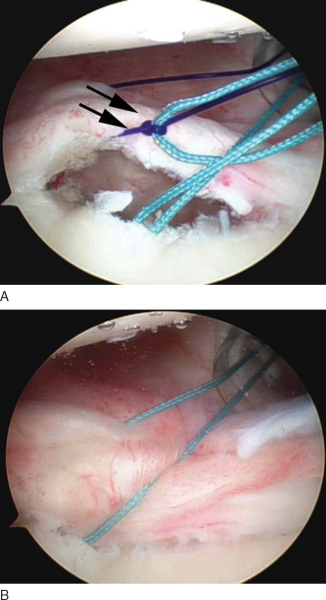

The next step is to pass a temporary suture that will be used subsequently to shuttle one limb of the permanent suture from the anchor through the tissue and labrum, which will secure the capsulolabral tissue back to the glenoid. Several arthroscopic instruments are commercially available to facilitate this step. We prefer to use a 45-degree curved suture shuttle (Spectrum Soft Tissue Repair System; ConMed Linvatec, Inc., Largo, Fla) through which a No. 1 PDS suture (Ethicon, Inc., Somerville, NJ) is passed (

Fig. 3-10

). It is important to place this shuttle stitch as inferior as possible to allow superior translation and retensioning of the capsulolabral complex onto the articular margin once it is tied. The suture delivery instrument is passed first through the capsule approximately 1 to 2 cm from the labrum. The hook is then passed through the labrum (

Fig. 3-10A

). The first passage will produce a capsular plication as it forms a pleat in the capsule. The second pass facilitates repair of the labrum back to the glenoid. The primary purpose of the shuttle suture is to serve as a temporary stitch that will then be used to pass one limb of the suture from the suture anchor to be passed through the tissue. Many instruments are available to allow the surgeon to skip this step by passing the instrument through the tissue to retrieve the suture from the previously placed anchor. However, use of a shuttle suture as described allows more precise placement of the sutures through the tissue.

At this point, one limb of the PDS shuttle suture and one limb of the permanent suture are exiting each of the anterior cannulas. Outside the anterosuperior portal cannula, the PDS suture is tied to the permanent suture several centimeters from the end (

Fig. 3-13

). A dilating knot can be made with a simple half-hitch to facilitate passage of the shuttle suture. Once secured, the PDS shuttle suture, along with the attached permanent suture, is pulled through the anteroinferior portal (

Fig. 3-14

). Arthroscopic visualization of this maneuver is important to ensure that the sutures do not become entangled during passage through the tissue. The PDS suture is now discarded, and both limbs of the permanent suture are exiting the anteroinferior portal, with one limb now through the soft tissue.

The knot pusher is again passed down one limb to ensure that the tails are not twisted around one another. An arthroscopic knot is now tied to secure the capsulolabral tissue back to the glenoid (

Fig. 3-15

). Many arthroscopic knots have been described; however, the surgeon should become proficient with one sliding-locking knot so it can be tied quickly and reproducibly with little effort. We prefer to use a modified Roeder knot that allows a strong suture buttress. This is backed up with three half-hitches to secure the knot. To reduce the tension on the tissue during tying, an atraumatic tissue grasper can be passed through the anterosuperior portal to translate the tissue while this first knot is tied. The tails of the completed knot are cut with the arthroscopic scissors passed through either the anterosuperior portal or the anteroinferior portal, depending on the optimal angle. This entire process is repeated two or three times to restore the tissue back to the glenoid. The knots should be secure and induce a dimpling effect on the capsulolabral tissue (

Fig. 3-16

).